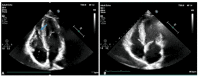

Figure 2. Transthoracic echocardiogram in the acute phase and after six months

2A. Transthoracic echocardiogram in four-chamber view revealing an oval-shaped mass (blue arrow) in the apex of the right ventricle 2B. Follow-up transthoracic echocardiogram after six months of adequate anticoagulation showing complete resolution of the thrombus